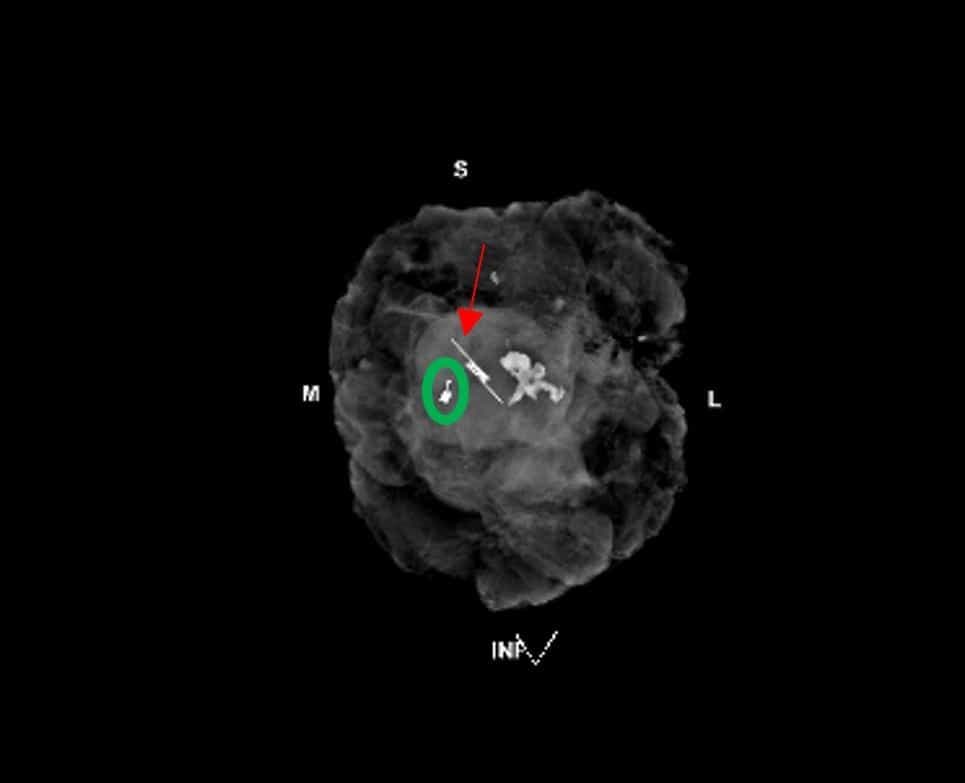

While there are several different wireless seed products in use, the technique is the same regardless of product used. A wireless seed is placed within or near the lesion and then the seed and lesion are surgically excised under the guidance of an intraoperative handheld seed-specific probe (Figure 1). This technique is a safe and feasible option for localization.

Figure 1. Left lumpectomy specimen radiograph. Red arrow: seed localization (Savi Scout®). Green Circle: radiopaque biopsy clip